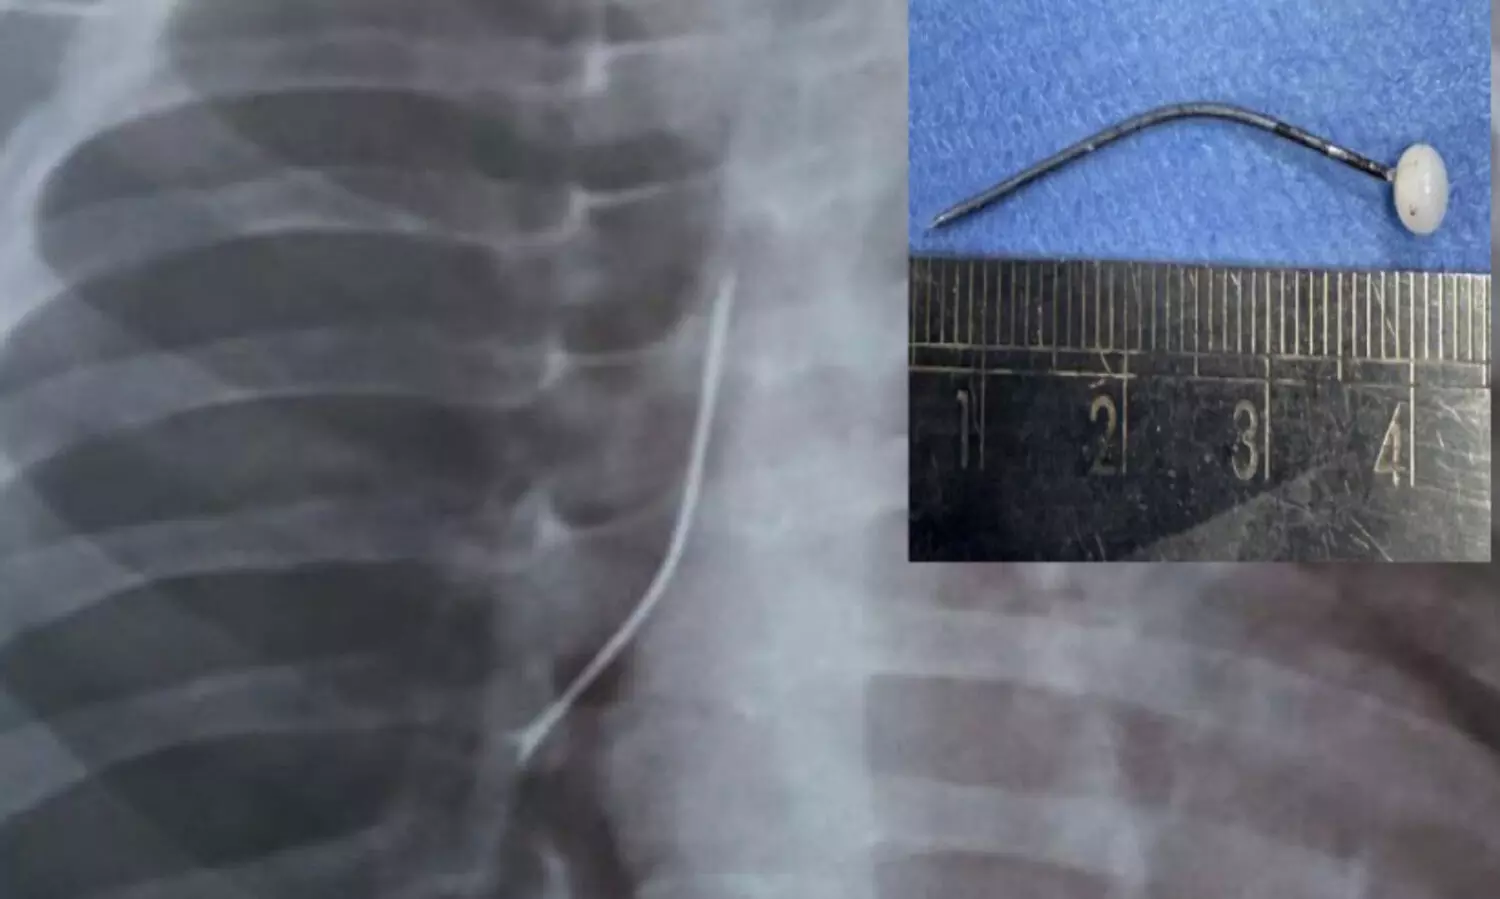

പിഞ്ചുകുഞ്ഞിന്റെ ശ്വാസനാളത്തിൽനിന്ന് നാല് സെന്റീമീറ്റർ നീളമുള്ള സേഫ്റ്റി പിൻ പുറത്തെടുത്തു